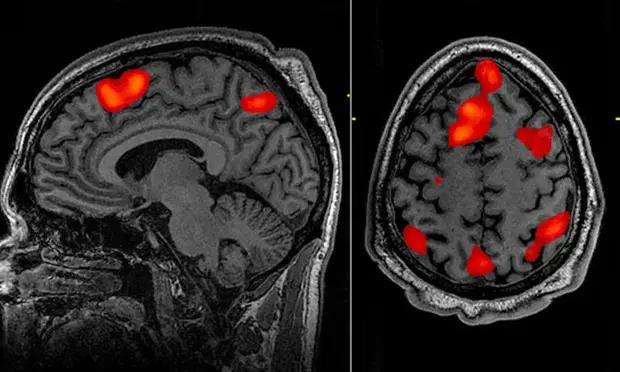

For the study, three people spent a total of 16 hours inside an fMRI machine listening to spoken narrative stories, mostly podcasts such as the New York Times’ Modern Love.

This allowed the researchers to map out how words, phrases and meanings prompted responses in the regions of the brain known to process language.

Because fMRI scanning is too slow to capture individual words, it collects a “mishmash, an agglomeration of information over a few seconds,” Huth said.

“So we can see how the idea evolves, even though the exact words get lost.”